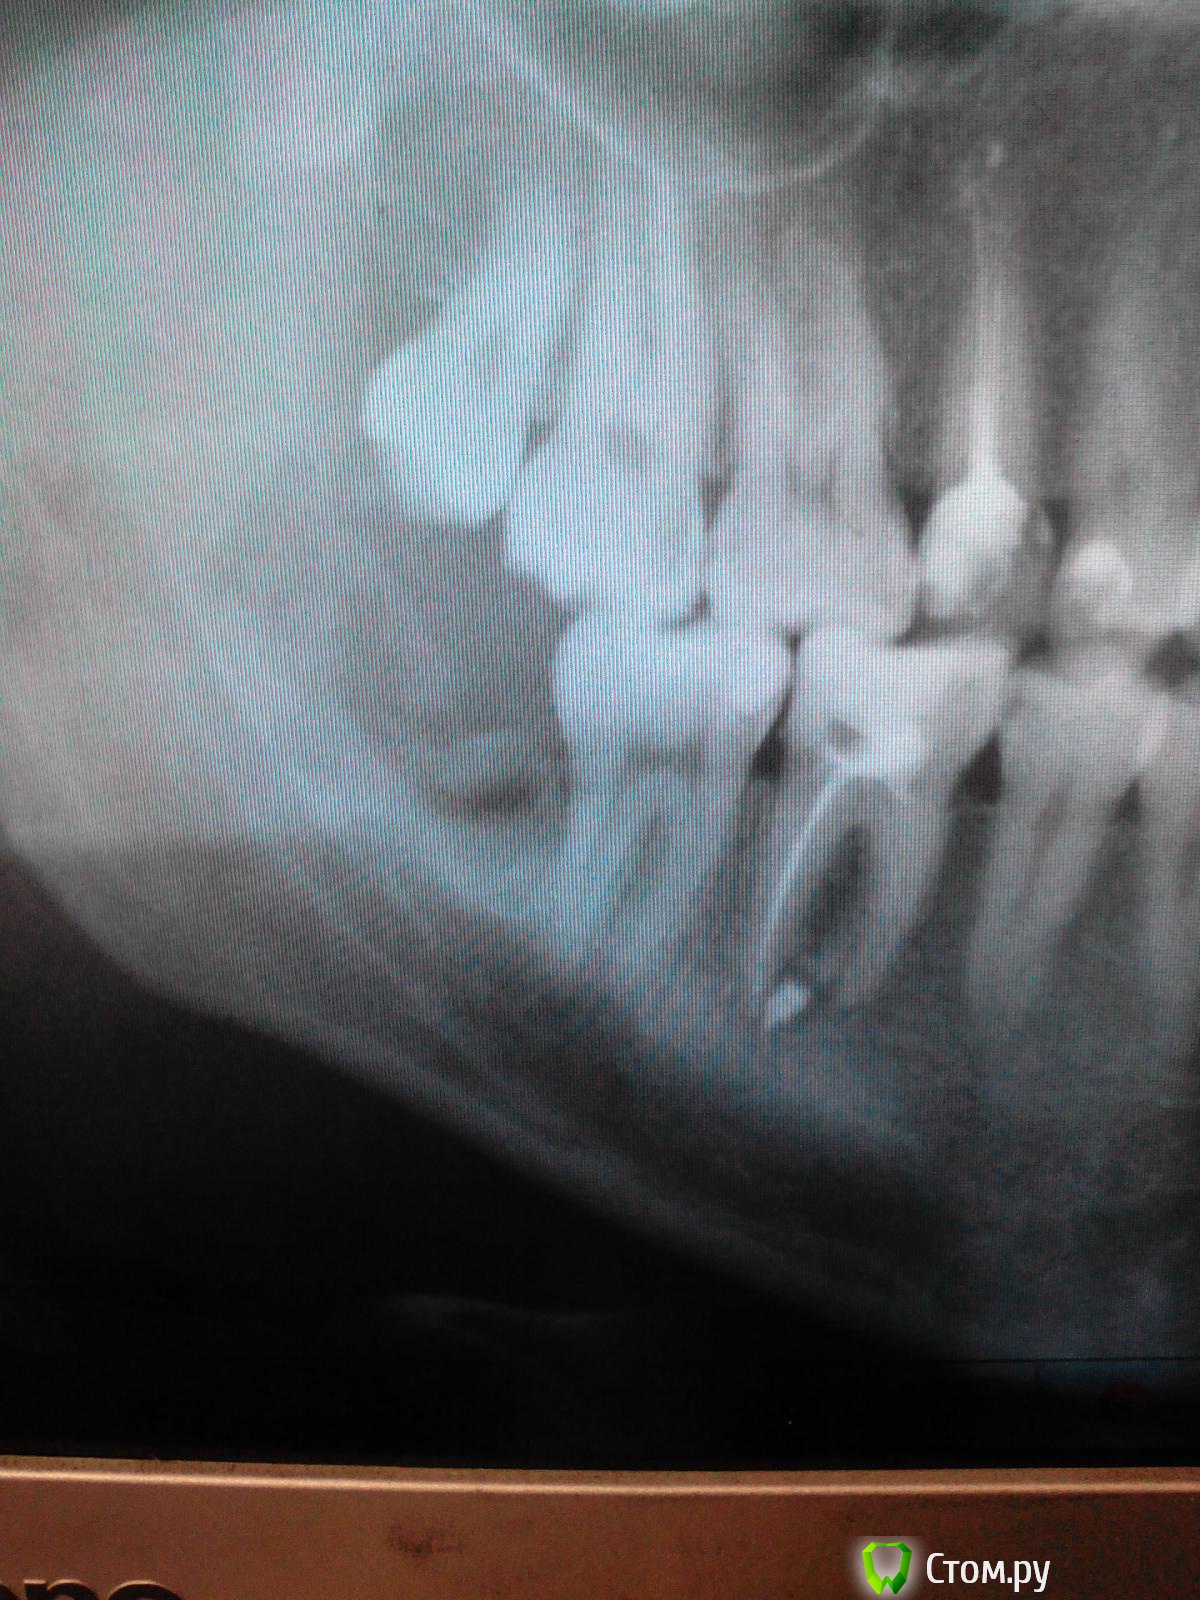

Alessandre2013 Опубликовано 6 февраля, 2014 Поделиться Опубликовано 6 февраля, 2014 Добрый день. Александр, 26 лет. Была полуретензия и дистопия зуба мудрости справа на нижней челюсти. Удаляли два месяца назад в течении полутора часов с дикой болью. Боль после удаления длилась 2 недели и в течении 2-х недель я пил диклофенак (когда через неделю я пришел ко врачу и сказал, что у меня пульсирующая невыносимая боль, отдающая в ухо и пол челюсти - он сказал, что все нормально). Изо рта был гнилостный запах и светло желтые выделения из места удаления зуба. Со временем стало получше. Однако челюсть так и не открывалась более 3 см. и пол языка не чувствую (до сих пор). На январских праздниках мне пришлось пойти снова к хирургу, т.к. там все начало кровоточить периодически и появились какие-то красные пузыри. Мне там всё (якобы) почистили. Назначили антибиотики. Поставили диагноз ограниченный остеомиелит лунки. Рентген сделали - зуб удален полностью и вообще всё чисто. Ситуация улучшилась. Челюсть смог растянуть до 4,5 см. Но буквально неделю назад начал появляться гнилостный запах и постоянно вкус гноя во рту. Решил посмотреть что там. Из лунки видны какие-то множественные красные воспаления. Нажал ватной палочкой на десну рядом - из того места пошел гной. И онемение языка усилилось как раз неделю назад. Сегодня был у врача. Сделали рентген (прилагаю). Посмотрев на рентген, ничего не сказав, назначили операцию на 18 марта. 18 марта я естественно ждать не буду, уже записался к другому хирургу в другую клинику на 18 февраля (ранее все расписано уже). Итак, вопрос: Что мне сейчас делать с лункой, чтобы хотя бы не запустить процесс и чтобы он не развивался дальше? Плюс еще впереди мой самый любимый праздник 14 февраля, который очень хочу провести нормально. Может стрептоцид положить туда, или метрогил-дента закладывать? Или просто полоскать? Если полоскать, то чем? И еще вопрос, что за темное пятно на месте удаленного зуба.Заранее благодарен за доброжелательный и развернутый ответ. Ссылка на комментарий

SergioS Опубликовано 6 февраля, 2014 Поделиться Опубликовано 6 февраля, 2014 Снимок малоинформативен! Ссылка на комментарий

Большой Зеленый Опубликовано 6 февраля, 2014 Поделиться Опубликовано 6 февраля, 2014 Похоже на корень. Т.е .неполное удаление.Срочно к доктору. 1 Ссылка на комментарий

diesel87 Опубликовано 6 февраля, 2014 Поделиться Опубликовано 6 февраля, 2014 Здравствуйте, снимок действительно малоинформативен, но такое ощущение что в лунке либо остаток корня зуба либо костная стенка осталась, если есть отделение гноя из лунки и онемение и так же рот открывается не в полном объеме, то возможно онемение либо из-за стойкого отека либо из-за стойкой анестезии, полоскания содо-солевым раствором поможет вымыть гной из лунки, а метрогил частично снимет воспаление, но к хирургу надо обязательно и до 18 февраля ждать бы тоже не советовал. Ссылка на комментарий

kriokov Опубликовано 6 февраля, 2014 Поделиться Опубликовано 6 февраля, 2014 Вот полный снимок (хотя тоже самое). Когда в начале января делали снимок, там этого пятна не было. корень там или свободный фрагмент косточки от лунки, суть одна-- Вам надо к врачу срочно Ссылка на комментарий